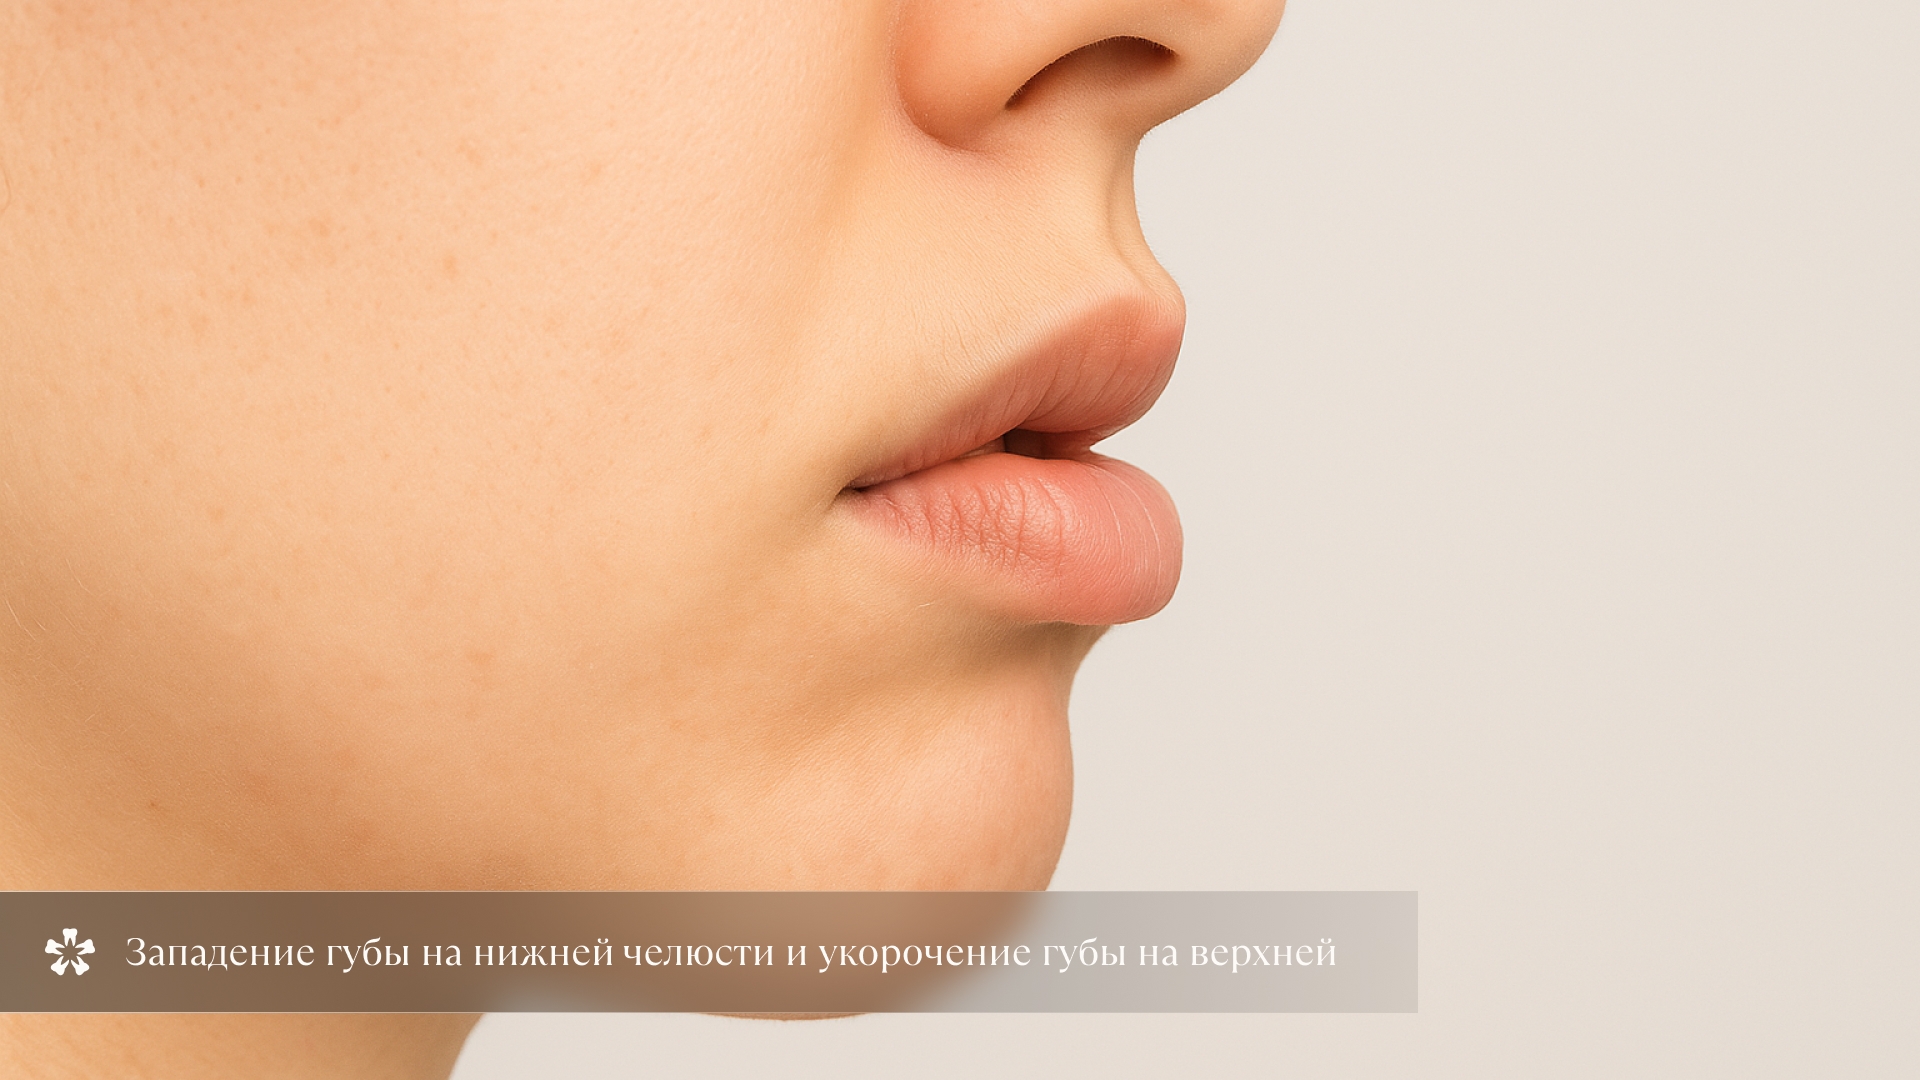

3. Выступание верхней губы

Западение нижней и выступание верхней губы. Фронтальная группа зубов резко выступает вперед.

4. Несмыкание губ

Очень часто дистальный прикус сопровождается наличием расстояния между верхними и нижними резцами — сагиттальной щелью, а также несмыканием губ из-за чего рот бывает слегка приоткрыт.